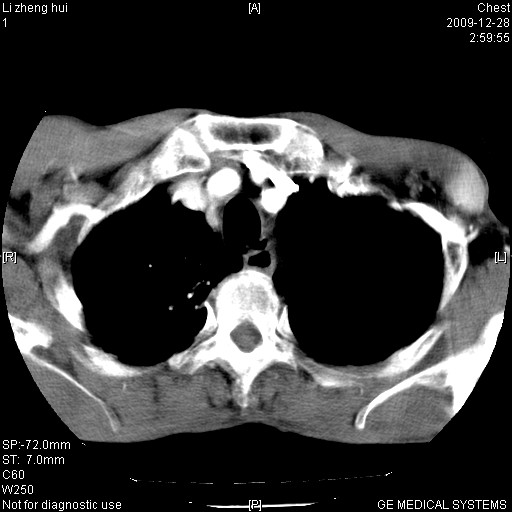

男  79岁 胸部痛急诊入院,晚上做的增强

考虑主动脉瘤?(增粗、钙化、壁血栓?)

支持降主动脉夹层

支持降主动脉瘤,不考虑夹层

1)考虑胸主动脉壁间血肿或夹层动脉瘤。2)多发性肝囊肿。

1)考虑胸主动脉附壁血栓或夹层动脉瘤。2)多发性肝囊肿。